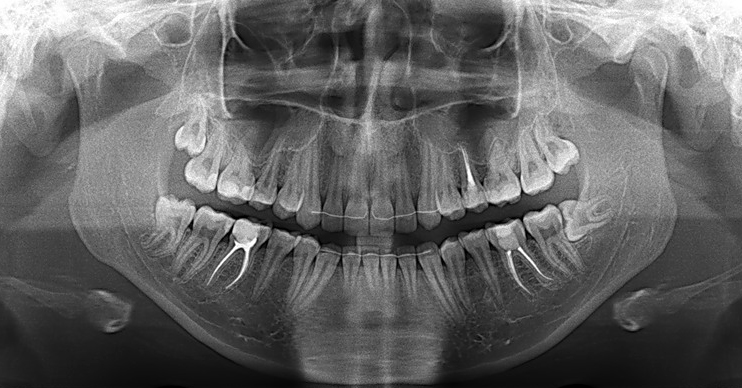

Дентальные снимки и диагностика кариеса